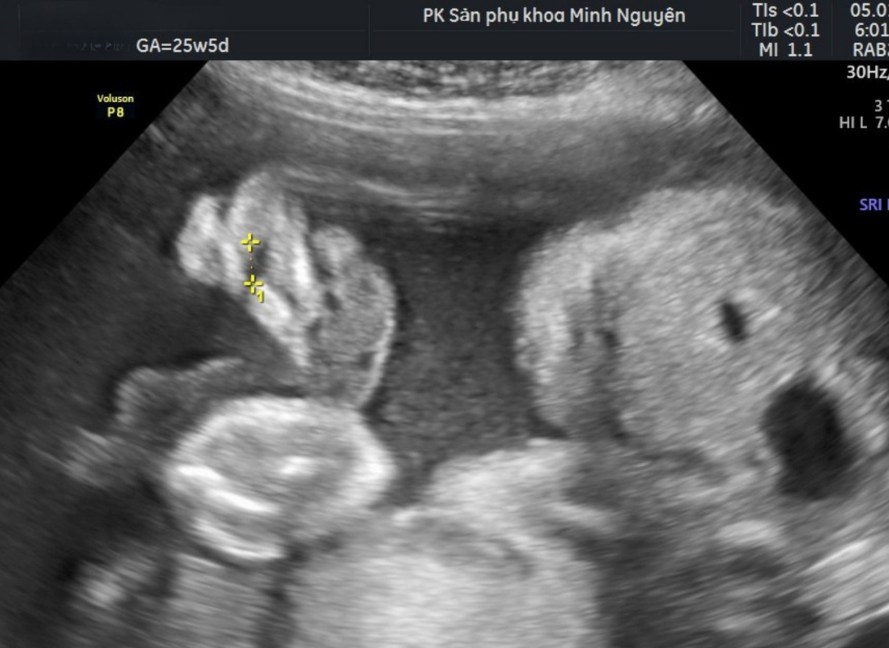

Hình ảnh sứt môi trên siêu âm

Sứt môi hở hàm ếch thường được phát hiện trong siêu âm hình thái quý II, khoảng 18–24 tuần, khi cấu trúc môi và cung răng được khảo sát đầy đủ. Ở những trung tâm có kinh nghiệm, sứt môi có thể nghi ngờ từ 11–13+6 tuần. Tuy nhiên, không phải tất cả các trường hợp đều phát hiện được ở quý I, và hở hàm ếch đơn thuần có thể khó chẩn đoán trước sinh.

Trên siêu âm, bác sĩ có thể thấy:

• Mất liên tục đường viền môi trên

• Khe hở ở vùng môi khi khảo sát mặt cắt mặt trước

• Một số dấu hiệu gián tiếp gợi ý hở hàm ếch

Siêu âm là chẩn đoán sứt môi hở hàm ếch, không chỉ là sàng lọc

Sứt môi hở hàm ếch là dị tật cấu trúc vùng mặt. Khi trên siêu âm quan sát rõ khe hở môi trên với sự gián đoạn liên tục của viền môi ở mặt cắt chuẩn. Đây được xem là chẩn đoán hình thái trước sinh, không phải dấu hiệu sàng lọc.

Khác với các dấu hiệu mềm như tăng âm ruột hay nốt tăng âm trong tim, sứt môi hở hàm ếch là bất thường giải phẫu nhìn thấy trực tiếp.

Tuy nhiên, siêu âm vẫn cần đánh giá kỹ mức độ lan rộng và khả năng kèm hở hàm ếch, vì tổn thương khẩu cái đơn thuần có thể khó phát hiện hơn trước sinh.

Hình ảnh siêu âm 4D sứt môi trên